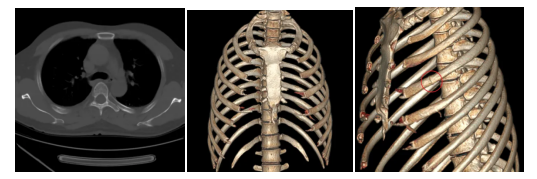

胸部外伤患者,左图为平扫CT,中图及右图三维CT容积重建。

平扫CT左侧肋骨骨折显示不清,三维CT容积重建清楚而直观地显示左侧第4肋骨骨折。胸部外伤胸片怀疑骨折以及伤情鉴定等必须明确骨折的情况下,胸部三维成像CT才能明确骨折的数量、形态、类型以及并发症等,是胸部外伤不可替代的检查方法,为患者的后续诊断及治疗提供依据,避免重复检查和不必要的医疗隐患。